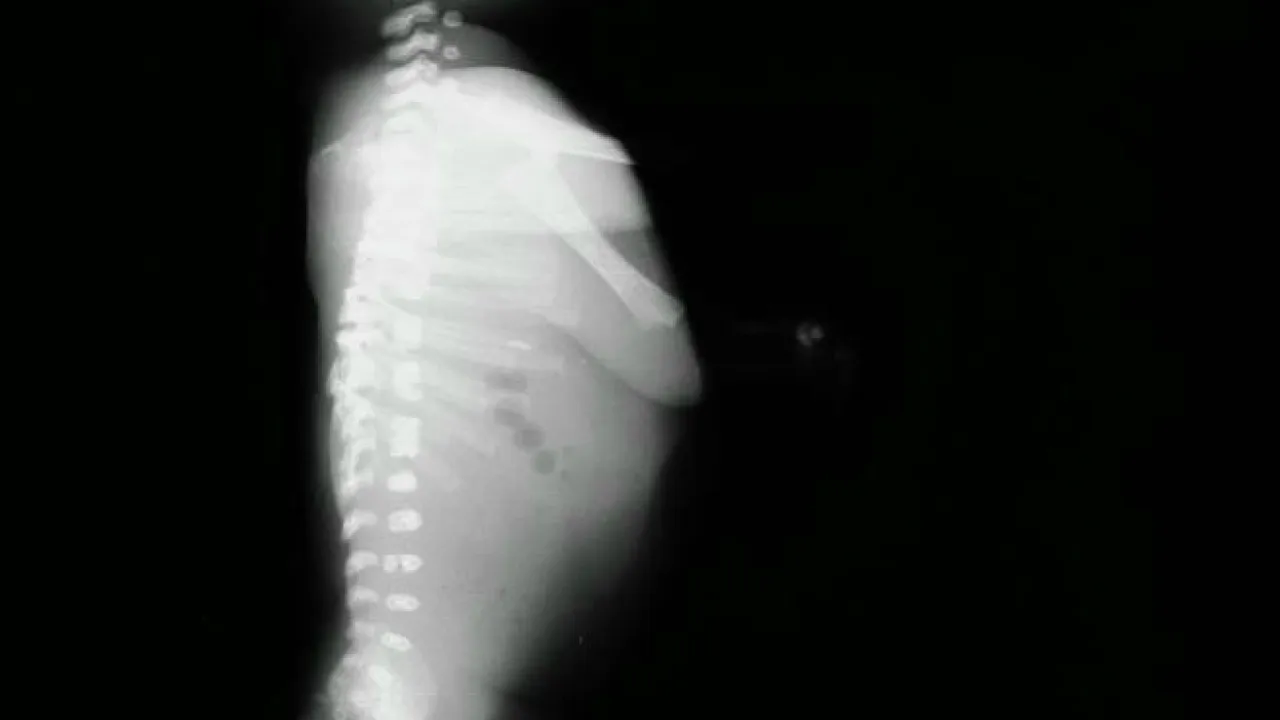

Bones, Hypophosphatasia

Bones, Hypophosphatasia, Sibling